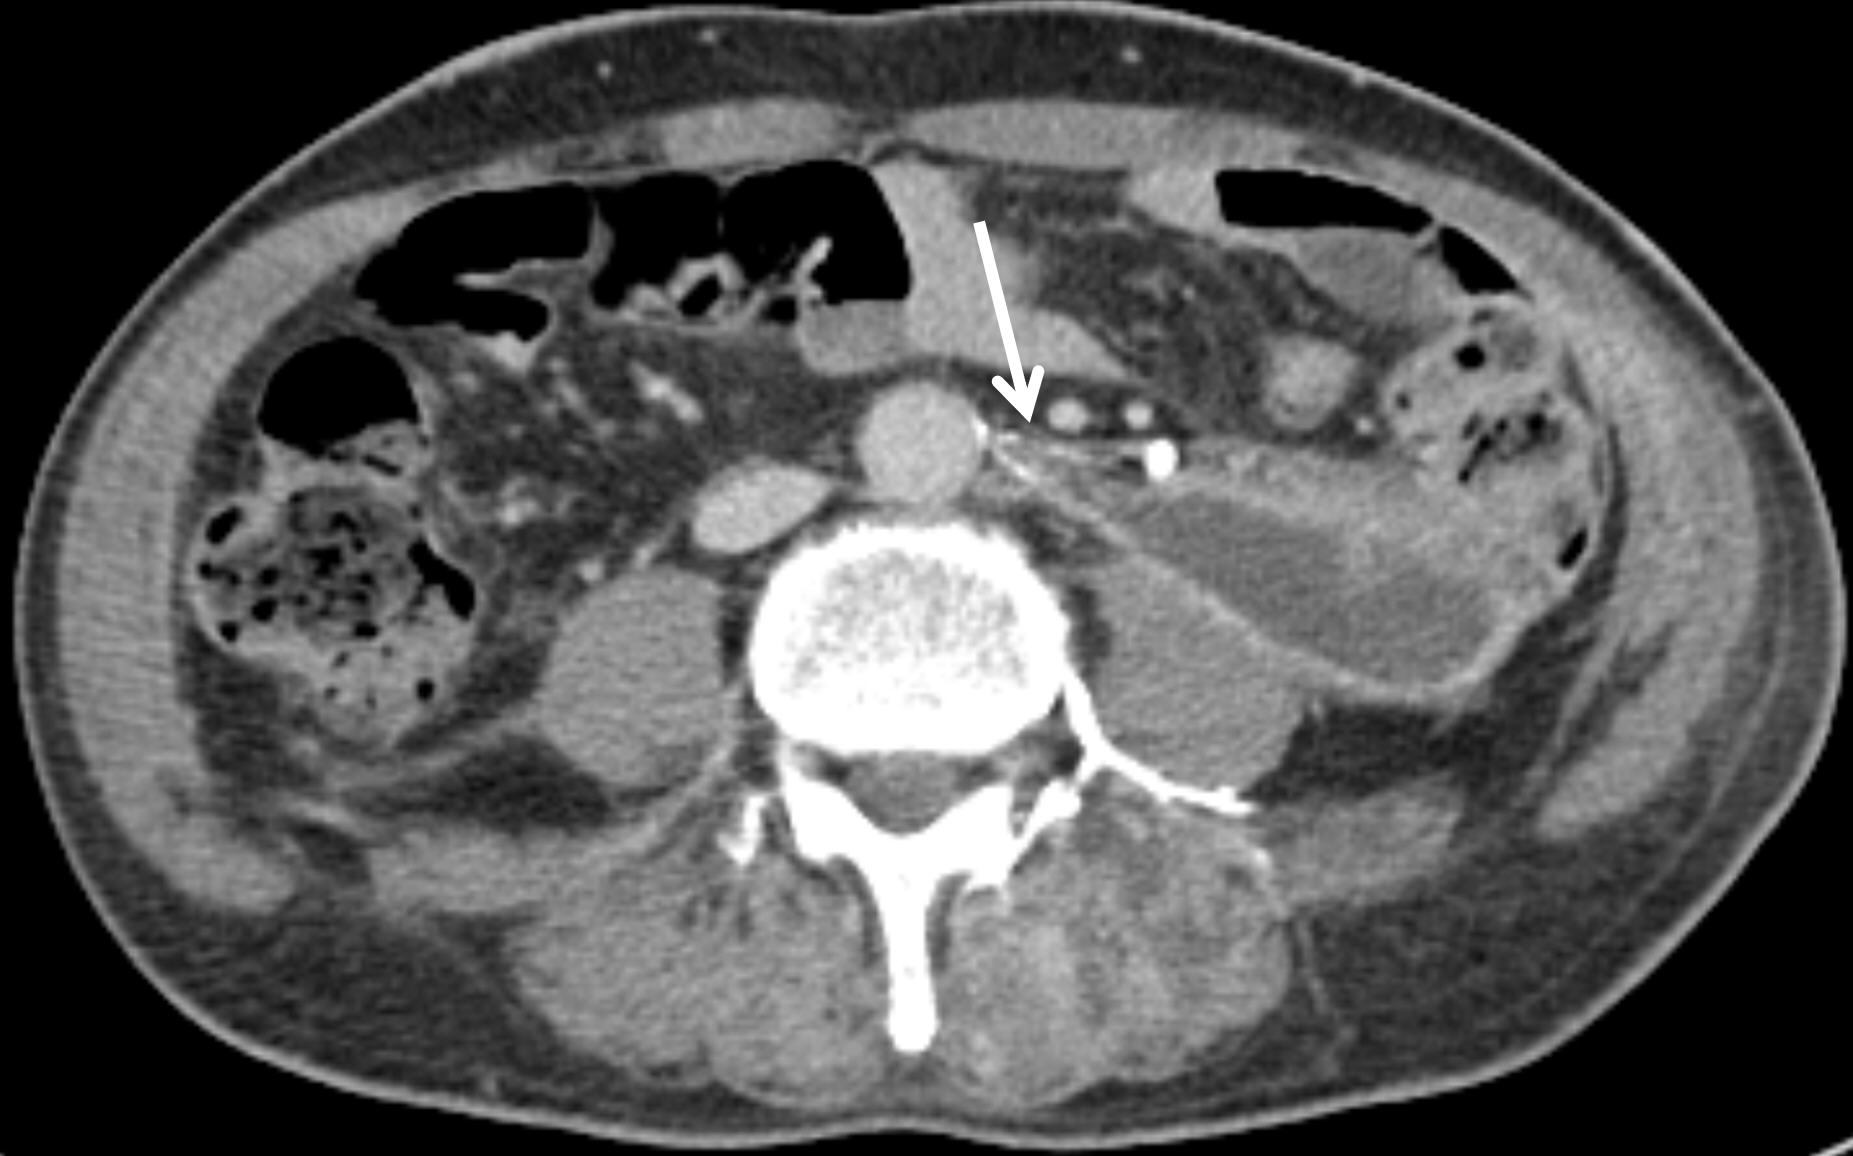

A 65-year-old male pedestrian presented to the level I trauma center emergency department following a motor vehicle collision. On arrival, his blood pressure was 60/40 mmHg and his heart rate was 120 beats per minute. Laboratory evaluation revealed a serum hemoglobin level of 12.6 g/dL, a platelet count of 237,000/mm

3, and an INR of 1.02. Contrast-enhanced thoracoabdominal CT, performed to identify possible bleeding sources, demonstrated a left retroperitoneal hematoma with active extravasation (

Fig. 1). Associated fractures were noted in the left iliac bone at the anterior superior iliac spine and the left transverse process of L5. There was no evidence of hematuria or hydronephrosis.

Fig. 1.Preprocedural contrast-enhanced abdominopelvic CT reveals a left retroperitoneal hematoma with associated contrast media extravasation (asterisk).